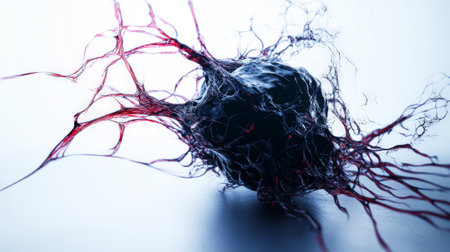

3d rendering of cancer cells in human body.cancer cell concept

Biological cancer cell and disease, 3d rendering. 3D illustration.

Growing cancer cell concept image. 3d rendering